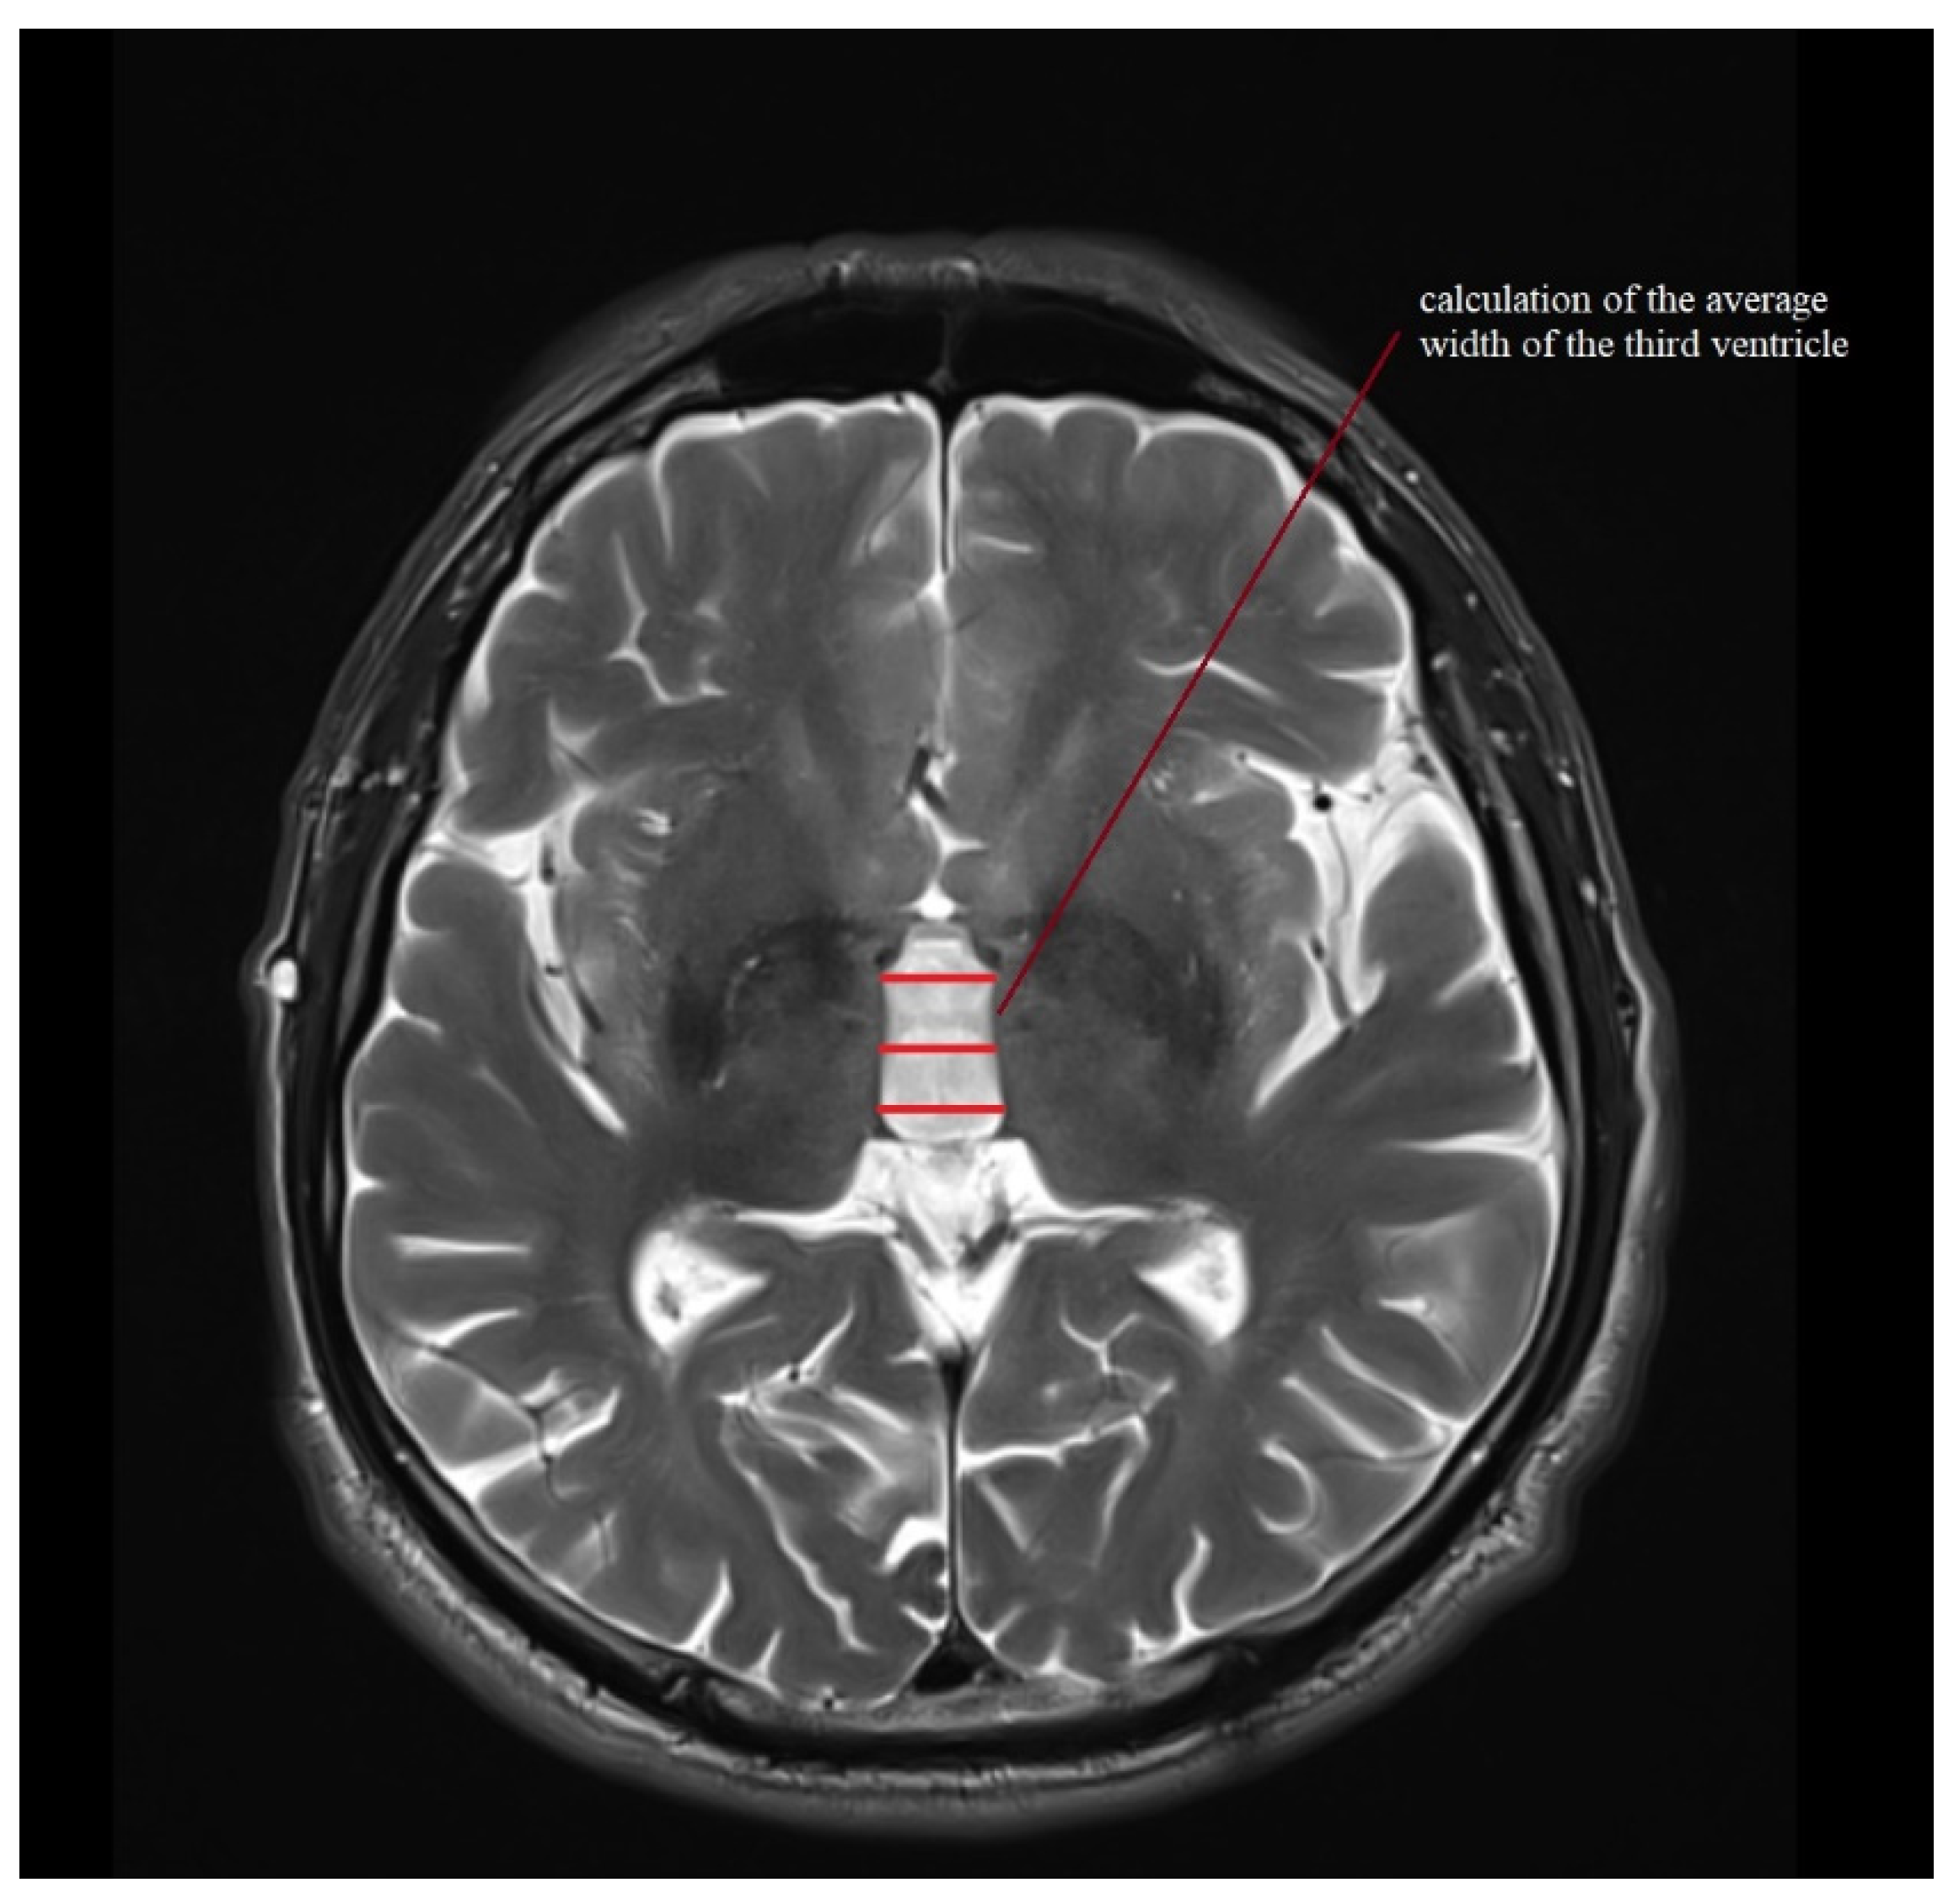

| III ventricle (mm) | 7.6 (4.2–12.5) | 2.2 ± 1.6–3.4 | 11.1 (6–16) | 2.5 ± 1.8–4 | 12.2 (5–19) | 3.1 ± 2.4–4.6 | 9.4 (6–14) | 2.5 ± 1.9–3.6 | 10.3 (7–14) | 2.1 ± 1.6–3.1 |